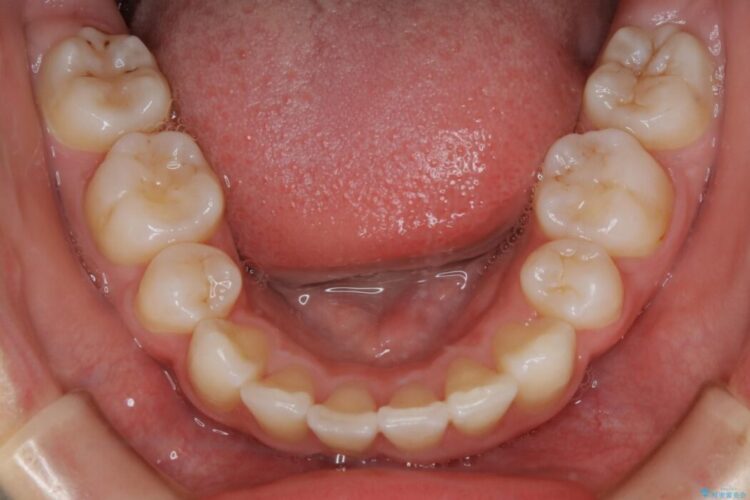

検査したところ歯に対して骨が上顎・下顎共に小さいことがわかりました。

それによりスペースが少なく歯列がガタついたり前方傾斜する生え方となっていました。

本症例の患者様は顎の骨が小さく歯をきれいに並べるための隙間がないため、歯が重なったり傾斜してしまっていました。